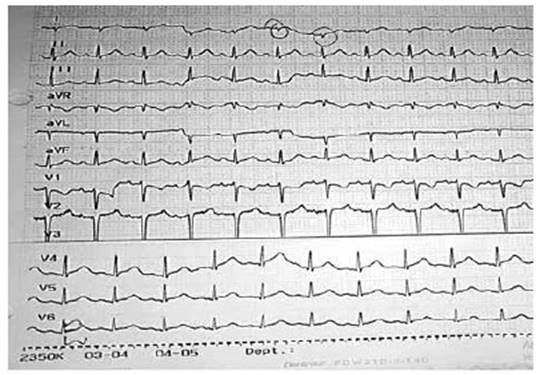

Ingresa a consultorio externo por presentar tiempo de enfermedad de 15 días con dolor de garganta, tos esporádica y cansancio, fiebre que cedía con Paracetamol; 2 días antes presenta diaforesis, malestar general y 1 día antes se agregan náuseas y vómitos más frialdad distal y dolor torácico. Es evaluado con FC: 145 x’, PA: 73/52 mmHg. taquipneico, pálido y con frialdad distal, los ruidos cardiacos con leve disminución del tono, no soplos, no visceromegalias; es referido a trauma shock de emergencia donde se le brinda fluidos en bolo Endovenoso, con dobutamina y noradrenalina. Y manejo antibiótico con ceftriaxona y macrólido Los exámenes auxiliares (Tabla 01) muestra: Hemograma leu 18410 /µL, Hemoglobina (Hb) 14.9gr/ dL, plaquetas: 322700 /µL, lactato 3.1 Ph 7.4 deshidrogenasa láctica(DHL): 1884 IU/L , alanina aminotransferasa (TGP): 1212 IU/L aspartato aminotransferasa (TGO): 1754 IU/L , creatina- fosfocinasa (CPK)total 3471 ng/ml, Troponina I: 7164 Pg/ml. IFI viral negativo, Core Total Hep B, hepatitis A IgM, hepatitis C (no reactivos) IgM para Mycoplasma Pneumonae (positivo) y Mycoplasma pneumonae (Reactivo). La Radiografía de tórax (Figura N°1) muestra leve cardiomegalia y refuerzo parahiliar derecho, el EKG (Figura N°2) se observó complejos QRS de bajo voltaje, taquicardia sinusal y leve supradesnivel del segmento ST. El ecocardiograma (Figura 3 A y B) efusión pericárdica moderada, dilatación de Vena cava inferior, pericardio engrosado, FEVI (fracción de eyección del ventrículo izquierdo) 66%, Ventrículo derecho disminuido. Con todo esto y los datos de laboratorio se establece el diagnostico de Miopericarditis.

Figura N°2 Electrocardiograma: muestra taquicardia sinusal, complejos QRS de bajo voltaje y leve supra desnivel de ST.

El Electrocardiograma (Ecg) es una herramienta sensible y económica para la evaluación inicial de casos sospechosos, ya que el diagnóstico de carditis puede no estar claro debido a la falta de síntomas cardíacos específicos, y en nuestro paciente se observó la taquicardia sinusal y los complejos de bajo voltaje y alteración del segmento ST. 3